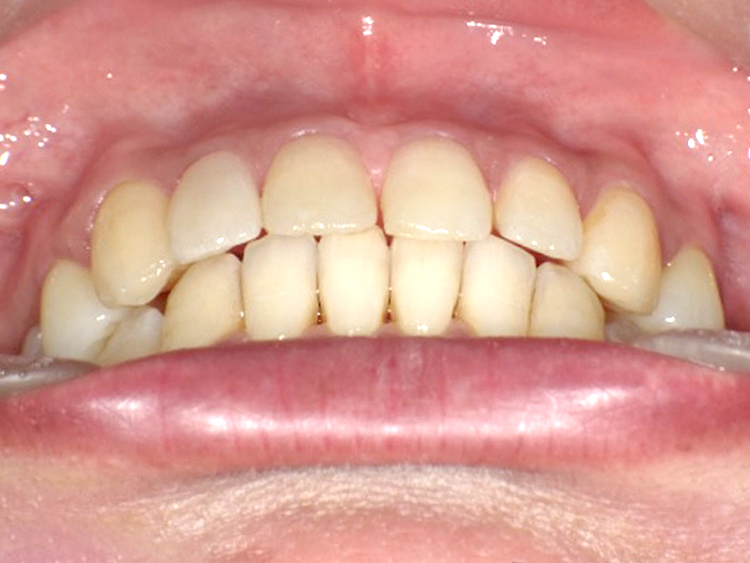

症例3

Before

After

| 主訴 | 上下の歯のガタガタを治したい |

|---|---|

| 年齢 | --- |

| 治療期間 | 約10ヶ月 |

| 治療内容 | インビザラインiGoで上下顎の治療。 狭まっていた歯並びを広げることで、 ガタガタに並んでいた歯を綺麗に並べた。 |

| 治療費 | ¥517,000(税込)+月額調整料 |

| 治療のリスク | 歯と歯の間を削ることでスペースを確保するので、 場合によっては歯が染みる症状が出ることがある。 |